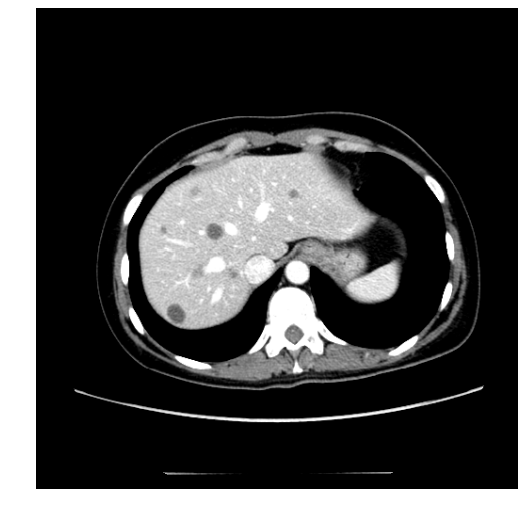

In clinical routine, manual or semi-manual segmentation techniques are applied to interprete CT and MRI images that have been acquired in the diagnosis of the liver. These techniques, however, are subjective, operator-dependent and very time-consuming. In order to improve the productivity of radiologists, computer-aided methods have been developed in the past. However, an automated robust segmentation of combined liver and lesion remains still an open problem because of challenges as a low-contrast between liver and lesion, different types of contrast levels (hyper-/hypo-intense tumors), abnormalities in tissues (such as after surgical resection of metastasis), size and varying number of lesions. As shown in figure 1 the heterogeneity in liver and lesion contrast is very large among subjects. Different acquisition protocols, differing contrast-agents, varying levels of contrast enhancements and dissimilar scanner resolutions lead to unpredictable intensity differences between liver and lesion tissue. This complexity of contrast differences make it difficult for intensity-based methods to generalize to unseen test cases from different clinical sites. In addition, the varying shape of lesions due to irregular tumor growth and response to treatment (i.e surgical resection) reduce efficiency of computational methods that make use of prior knowledge on lesion shape.

Figure 1: Liver and liver lesions slices in CT and diffusion weighted DW-MRI as well as the corresponding histogram for liver and lesions pixels in the respective modality. The shape, size and level of contrast vary for different lesions. As the histograms indicate, there is a significant overlap between liver and lesion intensities, leading to a low overall contrast.